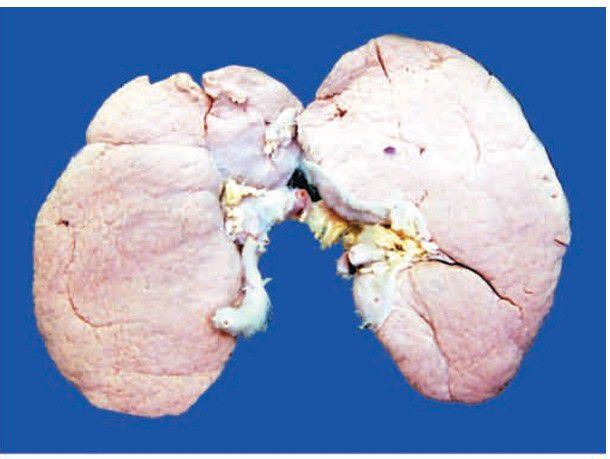

Chronic glomerulonephritis

End-stage kidney, gross appearance of short contract kidney in chronic glomerulonephritis. The kidney is small and contracted. The capsule is adherent to the cortex and has diffusely granular cortical surface.